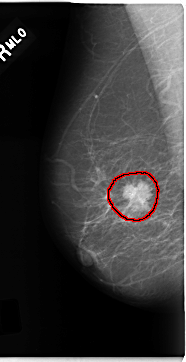

| FILE: C_0181_1.RIGHT_MLO.OVERLAY TOTAL_ABNORMALITIES 1 ABNORMALITY 1 LESION_TYPE MASS SHAPE IRREGULAR MARGINS SPICULATED ASSESSMENT 5 SUBTLETY 5 PATHOLOGY MALIGNANT TOTAL_OUTLINES 1 BOUNDARY |